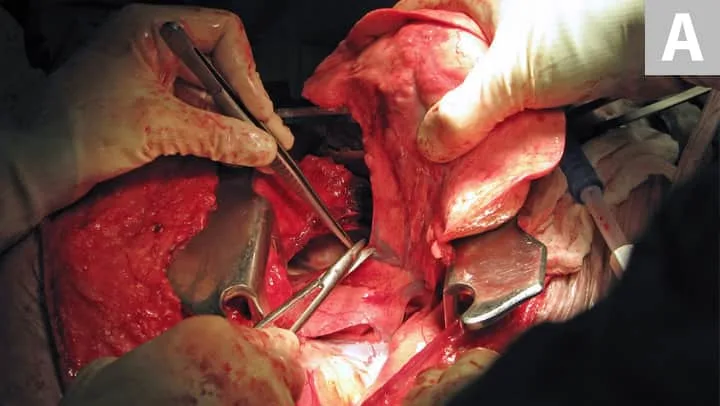

If adequate margins cannot be achieved with a wide excision of STS, consideration should be given for marginal or radical excision. Radical excision is the removal of an entire anatomical segment (eg, limb amputation). Many antebrachial STS can be successfully removed without amputation by employing wide excision with antebrachial fascia as the deep barrier. This defect can be reconstructed with a free skin graft or another skin-reconstruction technique2 (Figure 1). If the mass is overlying the carpus or elbow, a marginal excision should be considered. In low- and intermediate-grade tumors and geriatric patients, this may be sufficient for long-term control.3 For high-grade tumors (III), consideration should be given to follow up with radiation therapy.4

(A) Antebrachial soft-tissue sarcoma that is treated with wide resection. Note the deep layer of antebrachial fascia that serves as the deep margin and a barrier to tumor cell invasion (arrow). The surgeon’s fingers to the right of the arrow are between the extensors of the antebrachium and the fascial layer that is deep to the tumor. (B) Reconstruction of defect after antebrachial soft-tissue sarcoma wide resection with a free skin graft